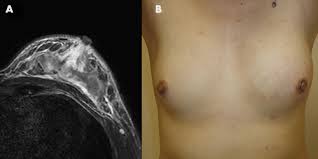

The features of a malignant breast condition on mri scan are often to do with the outer irregular borders of a lesion. Inflammatory breast cancer affects breast tissue and can appear unusually dimpled or thick. Absence of lump or breast mass in a patient suffering from an inflammatory skin condition of the breast, suggests the presence of skin or subcutaneous inflammatory condition caused by either infection or inflammatory breast cancer. The skin looks like the skin of an orange, and may be discolored with painful and itchy breast. The breast is enlarged (often of relatively short onset), indurated, erythematous, warm, and may be tender and painful. But not every woman who has been diagnosed with breast cancer needs a breast mri. What does breast cancer look like on a mammogram? A lump in the breast. Breast mri is sometimes used in women who already have been diagnosed with breast cancer, to help measure the size of the cancer, look for other tumors in the breast, and to check for tumors in the opposite breast. Most cases are invasive ductal carcinomas, which develop in the cells lining the milk ducts and spread throughout the breast. The breast can also be painful in inflammatory breast cancer, but this is not always the case. Evaluating the impact of preoperative breast magnetic resonance imaging on the surgical management of newly diagnosed breast cancers. When the cancer grows into the rest of the body through the blood vessels and lymph vessels, breast cancer spreads.

Inflammatory breast cancer affects breast tissue and can appear unusually dimpled or thick. Clinically, inflammatory breast cancer mimics mastitis. Breast infections can cause redness and swelling. They're often easy to move around (mobile) and may be tender. Inflammatory breast cancer (ibc) is rare, making up about 2 to 4 percent of breast cancer cases.

Unlike traditional forms of breast cancer, inflammatory breast cancers do not develop unusual lumps within the affected breast.

Inflammatory breast cancer is an an aggressive and fast growing breast cancer in which cancer cells infiltrate the skin and lymph vessels of the breast. They're often easy to move around (mobile) and may be tender. Ibc symptoms are caused by cancer cells blocking lymph vessels in the skin causing the breast to look inflamed. symptoms include breast swelling, purple or red color of the skin, and dimpling or thickening of the skin of the breast so that it may look and feel like an orange peel. Unlike traditional forms of breast cancer, inflammatory breast cancers do not develop unusual lumps within the affected breast. The skin is thickened and edematous, classically with a peau d'orange appearance. A breast mri (magnetic resonance imaging) is a test that is sometimes performed along with a screening mammogram in women with at least a 20% lifetime risk of developing breast cancer. What does breast cancer look like on a mammogram? Mri of breast can help breast cancer diagnosis. Inflammatory breast cancer inflammatory breast cancer is a rare type of breast cancer that develops rapidly, making the affected breast red, swollen and tender. A rash isn't the only visual symptom of inflammatory breast cancer. Inflammatory breast cancer (ibc) is rare, making up about 2 to 4 percent of breast cancer cases. Inflammatory breast cancer pictures and symptoms The skin looks like the skin of an orange, and may be discolored with painful and itchy breast.

The Radiology Assistant Mri Of The Breast from radiologyassistant.nl Inflammatory breast cancer pictures and symptoms The breast can also be painful in inflammatory breast cancer, but this is not always the case. The skin of the breast may also appear pink, reddish purple, or bruised. Ridges or thickening of the skin of the breast. Inflammatory breast cancer (ibc) is rare, making up about 2 to 4 percent of breast cancer cases. Need to have physical exam, mammogram, and ultrasound as needed. Sometimes it can be difficult to tell the difference between mastitis and inflammatory breast cancer. Absence of lump or breast mass in a patient suffering from an inflammatory skin condition of the breast, suggests the presence of skin or subcutaneous inflammatory condition caused by either infection or inflammatory breast cancer.